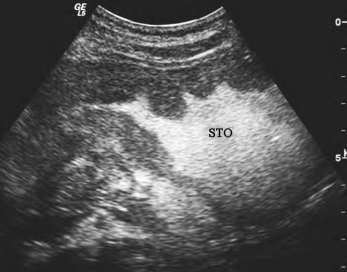

(2)胃体胃窦癌:胃壁局限性或弥漫性不规则增厚,癌肿可突入胃腔或向胃外生长,形态可分为隆起型、溃疡型及弥漫型,病变区胃腔可狭窄(图27-6)。

图27-6 胃窦癌声像图超声示意图

胃窦部胃壁局限性不规则增厚,致幽门狭窄,造影剂潴留。STO:胃